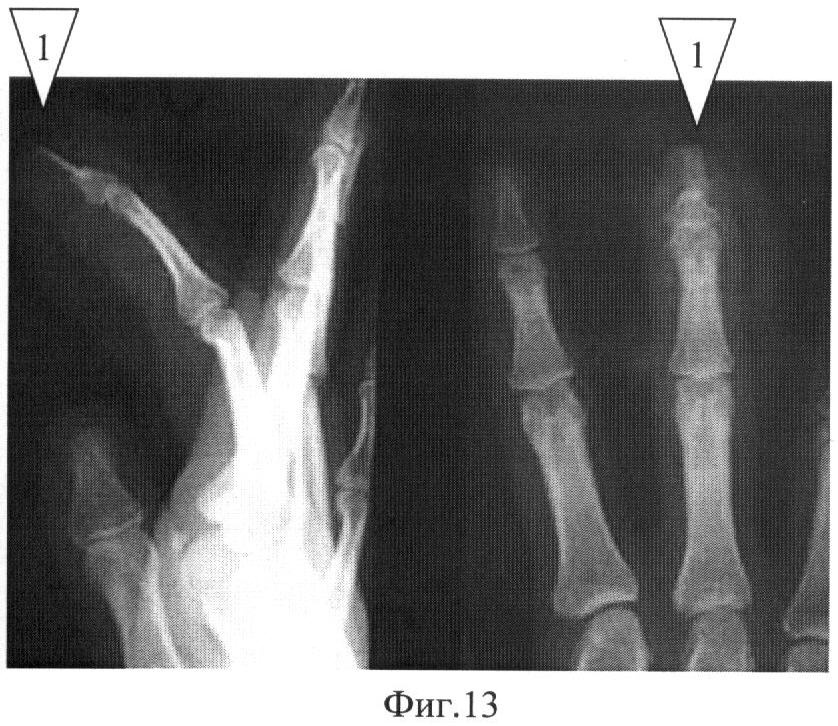

Изобретение относится к области медицины, а именно к травматологии и ортопедии, и может быть использовано для лечения пациентов с когтевидной деформацией ногтевых фаланг пальцев кисти. Для ликвидации когтевидной деформации, возникающей вследствие утраты дистальной части кости ногтевой фаланги, являющейся опорной основой для растущего ногтя при сохранении проксимального отдела ногтевого ложа, предложены различные способы оперативного лечения. Так, одним из способов является перемещение ногтевого комплекса в проксимальном направлении (Белоусов А.Е. // Пластическая, реконструктивная и эстетическая хирургия. - СПб.: Гиппократ, 1998, стр.411-412; Verdan C.E., Egloff D.V. // Fingertip injuries // Surg. Clin. N. Amer. - 1981. - Vol. 61, №2. - P.237-266). Ноготь с небольшим ладонным лоскутом приподнимают и сформированный длинный тыльный лоскут перемещают в проксимальном направлении. На ладонную поверхность пальца пересаживают перекрестный лоскут с соседнего пальца. После заживления раны удаляют избыток мягких тканей на тыле пальца. Недостатками данного метода являются: относительное укорочение длины пальца, донорский дефект на соседнем пальце, нарушение кожной чувствительности в месте пластики перемещенным лоскутом, необходимость повторных оперативных вмешательств для отсечения ножки лоскута и удаления избытка мягких тканей. Данная операция является аналогом предлагаемого нами способа. Известен способ коррекции когтевидной деформации ногтя путем остеопластического удлинения дистальной фаланги пальца. На ладонно-торцевой поверхности культи формируют и приподнимают кожный лоскут, включающий ткани ногтевого ложа и ногтевую пластинку; с помощью тонкой спицы фиксируют к костной культе дистальной фаланги пальца предварительно взятый некровоснабжаемый костный трансплантат, функция которого состоит в обеспечении последующей поддержки растущего ногтя. Затем ладонный дефект тканей закрывают скользящим ладонным пальцевым лоскутом (Белоусов А.Е. Пластическая, реконструктивная и эстетическая хирургия. - СПб.: Гиппократ, 1998, стр.411-412). Этот метод имеет существенные недостатки. В частности, необходимость выделения сосудисто-нервных пучков на протяжении всего пальца приводит к выраженному отеку и лимфостазу в лоскуте в послеоперационном периоде, что часто сопровождается нарушением чувствительности и трофики дистальных отделов пальца. Также ладонный пальцевой скользящий лоскут возможно сместить в область реконструкции только при сгибании пальца в проксимальном межфаланговом суставе. Это неизбежно приводит к сгибательной контрактуре последнего за период послеоперационной иммобилизации. Данный вид оперативного лечения является прототипом предлагаемого нами способа. Техническим результатом изобретения является: отсутствие травматизации дополнительного донорского участка на соседнем пальце для замещения дефекта кожи ногтевой фаланги; предотвращение развития недостаточности трофики и иннервации дистальных отделов пальца; отсутствие сгибательной контрактуры проксимального межфалангового сустава оперируемого пальца; возможность устранения подобных деформаций на любом пальце; хороший косметический результат и удовлетворение высоких требований пациента к качеству жизни. Результат изобретения достигается за счет того, что в качестве костного аутотрансплантата используют кортикальный трансплантат прямоугольной формы из нижней трети лучевой кости одноименной конечности, размерами около 1,0×0,5×0,3 см (в случае дефекта ногтевой фаланги 1п. - до 1,5×0,5×0,3 см), что позволяет выполнять оперативное вмешательство на одном сегменте без дополнительной анестезии. Дефект кожи ногтевой фаланги пальца восстанавливают посредством несвободной пластики островковым перемещенным кожно-жировым лоскутом на двух собственных сосудисто-нервных пучках. Данный лоскут возможно смещать в дистальном направлении на расстояние до 1,5 см и восстанавливать дефекты площадью до 2,5 см. «Подушечку» пальца формируют по типу «капюшона» при сведении дистальных краев трансплантата, а проксимальный отдел раны ушивают в линию без образования дефекта кожи, что обеспечивает хорошие функциональный и косметический результаты (V-Y пластика) (Furlow L.T. Journal of hand surgery - Ediburg, Scotland - 9(3); 253-6, 1984 Oct.). Реконструктивное вмешательство осуществляют в ходе одной операции. На чертежах изображены: Фиг.1 - формирование и подъем кожного лоскута на торце ногтевой фаланги, включающего ткани ногтевого ложа и ногтевую пластинку; Фиг.2 - подготовка костномозгового канала в сохранившейся костной части ногтевой фаланги, где 2 - это канал в костной части основания ногтевой фаланги; Фиг.3 - взятие костного аутотрансплантата из кортикальной пластинки дистального метаэпифиза лучевой кости, размерами около 1,0×0,5×0,3 см, где 1 - это костный аутотрансплантат из кортикальной пластинки дистального метаэпифиза лучевой кости; Фиг.4 - внедрение костного аутотрансплантата в подготовленный канал основания ногтевой фаланги, где 1 - это костный аутотрансплантат из кортикальной пластинки дистального метаэпифиза лучевой кости; Фиг.5 - формирование островкового несвободного кожно-жирового лоскута эллипсовидной формы с V-образным дистальным отделом на двух собственных сосудисто-нервных питающих ножках и смещение его в дистальном направлении, где 3 - это две собственные сосудисто-нервные питающие ножки; Фиг.6 - сведение двух дистальных точек кожного лоскута между собой с образованием чаши, необходимой для формирования контура подушечки ногтевой фаланги, где 3 - это две собственные сосудисто-нервные питающие ножки; Фиг.7 - вид пальца сбоку после ушивания послеоперационной раны; Фиг.8 - вид пальца с ладонной стороны после ушивания послеоперационной раны; Фиг.9 - клинический пример: вид пальца сбоку до операции; Фиг.10 - вид с тыла кисти до операции; Фиг.11 - вид пальца сбоку после снятия швов; Фиг.12 - вид с ладонной поверхности после снятия швов; Фиг.13 - рентгенологическая картина кисти в двух проекциях через 6 месяцев после операции, где 1 - это костный аутотрансплантат из кортикальной пластинки дистального метаэпифиза лучевой кости, внедренный в основание ногтевой фаланги; Фиг.14 - вид пальца с ладонной поверхности (6 месяцев после операции); Фиг.15 - вид пальца сбоку (6 месяцев после операции). Способ осуществляется следующим образом. Оперативное вмешательство производится под проводниковой анестезией в аксиллярной области, положение больного на спине, рука укладывается на приставной столик. Первым моментом является формирование и подъем кожного лоскута на торце ногтевой фаланги, включающий ткани ногтевого ложа и ногтевую пластинку; иссечение патологического рубца на подушечке пальца (Фиг.1). Вторым моментом производится формирование канала в сохраненной костной части ногтевой фаланги (Фиг.2). Третьим - взятие костного трансплантата из кортикальной пластинки дистального метаэпифиза лучевой кости одноименной конечности размерами около 1,0×0,5 см прямоугольной формы (Фиг.3). Четвертым - внедрение костного трансплантата в сформированный канал в основании ногтевой фаланги (Фиг.4). Пятым - формирование островкового кожно-жирового лоскута эллипсовидной формы с V-образным дистальным отделом на двух собственных сосудисто-нервных питающих ножках путем разрезов по нейтральным линиям пальца от кончика в проксимальном направлении до уровня дистального межфалангового сустава и затем по ладонной поверхности пальца к кожной складке до проксимального межфалангового сустава. Лоскут отслаивается от оболочки сухожилия сгибателя, образуя островок на двух сосудисто-нервных ножках (Фиг.5). Шестым моментом - сшивание двух дистальных точек кожного лоскута между собой с образованием чаши, необходимой для формирования контура «подушечки» ногтевой фаланги. Лоскут перемещается в зону дефекта, подшивается к ногтевой пластинке (части ногтевой пластинки или ногтевому ложу); образующийся дефект на средней фаланге ушивается с формированием Y-образной раны (V-Y пластика) (Фиг.6, 7, 8). Иммобилизация шиной до основания средней фаланги на срок до 8 недель (костного сращения по результатам контрольной рентгенографии). Клиническое наблюдение (Фиг.9-15). Больная К., 20 лет, № истории болезни 5192, ДЗ: Порочная культя 3 пальца правой кисти. Операция 26.04.07: Костная аутопластика ногтевой фаланги 3 пальца правой кисти трансплантатом из правой лучевой кости, несвободная пластика кожи ногтевой фаланги перемещенным островковым кожно-жировым лоскутом на двух собственных сосудисто-нервных пучках (V-Y пластика по Фурлоу). Время операции составило 1 час. Послеоперационный период протекал гладко, раны зажили первичным натяжением. Швы сняты на 14 сутки. Прирост длины ногтевой фаланги составил около 0,5 см. Иммобилизация гипсовой лонгетой осуществлялась 8 недель (до признаков консолидации по результатам контрольной рентгенографии). После снятия иммобилизации проведен курс реабилитационного лечения (ЛФК, ФТЛ). Достигнут хороший эстетический и функциональный результат (после проведенного курса реабилитационной терапии). Пациентка довольна результатом лечения.